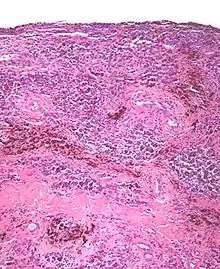

| Micrograph of diffuse TGCT, also known as pigmented villonodular synovitis. H&E stain. | |